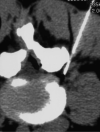

F<sc>ig</sc> 3.

Fig 3.

After intraforaminal infiltration, the gas mixture is distributed between the posterior longitudinal ligament and the dural sheath.